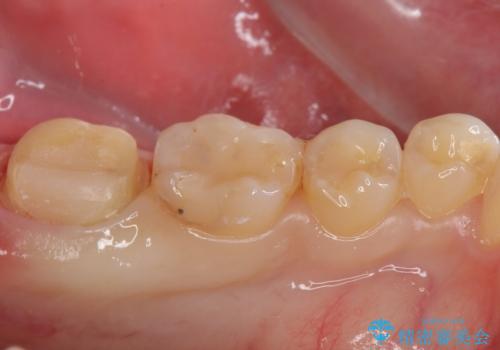

- 左下7 生活歯髄療法:33,000円 仮歯+ジルコニアクラウン:11,000円+121,000円費用は治療当時の料金となります

虫歯が大きくても、今回のように神経を温存することができる場合があります。